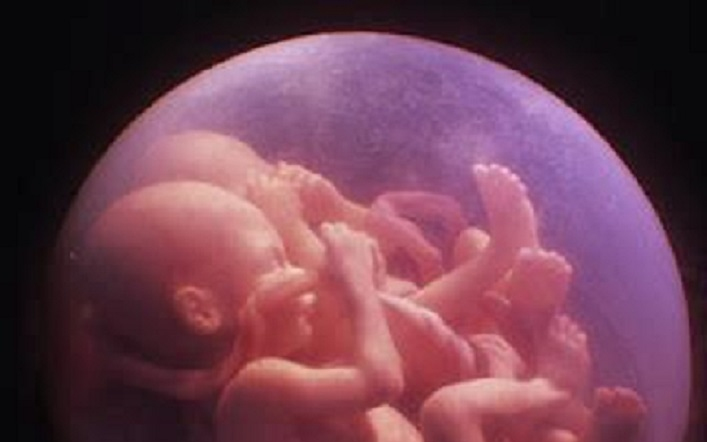

Ikerterhessége 20. hetében az orvosok közölték egy angol kismamával, hogy a vetélés elkerülhetetlen. Az ultrahang-vizsgálat során kiderült, hogy az egyik kislány, Kiki szívproblémával küzd, és úgy látták, hogy a méhlepényből folyadék szivárog. Úgy tűnt, 20 hetesen nem lenne esélyük a túlélésre, ezért mindenki felkészült a legrosszabbra.

Csodálatos módon azonban a másik iker, Nico mintha csak megérezte volna, hogy baj van: úgy helyezkedett a méhben, hogy elzárta a szivárgás útját, ezzel megvédte magát és kishúgát. Az orvosok nem akartak hinni a szemüknek, mikor a legközelebbi ultrahang-vizsgálaton kiderült, hogy Nico egészséges. A felvételekkel egészen a babák születéséig követték, ahogy Nico nem is mozdult el az „őrségből”.

A 30. héten végül császármetszést hajtottak végre az orvosok. Nico született meg először, majd öt perccel később Kiki, mindketten másfél kilogramm körüli súllyal. Az orvosok szerint ez már szép súlynak számít, amelyet annak a tíz hétnek köszönhettek, amíg Nico benntartotta magát és testvérét a méhben.